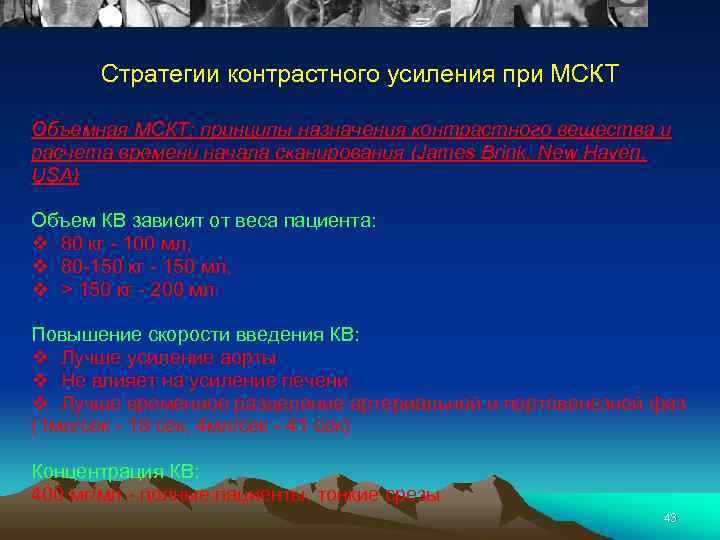

Стратегии контрастного усиления при МСКТ Объемная МСКТ: принципы назначения контрастного вещества и расчета времени начала сканирования (James Brink, New Haven, USA) Объем КВ зависит от веса пациента: v 80 кг - 100 мл, v 80 -150 кг - 150 мл, v > 150 кг - 200 мл Повышение скорости введения КВ: v Лучше усиление аорты v Не влияет на усиление печени v Лучше временное разделение артериальной и портовенозной фаз (1 мл/сек - 18 сек, 4 мл/сек - 41 сек) Концентрация КВ: 400 мг/мл - полные пациенты, тонкие срезы 43